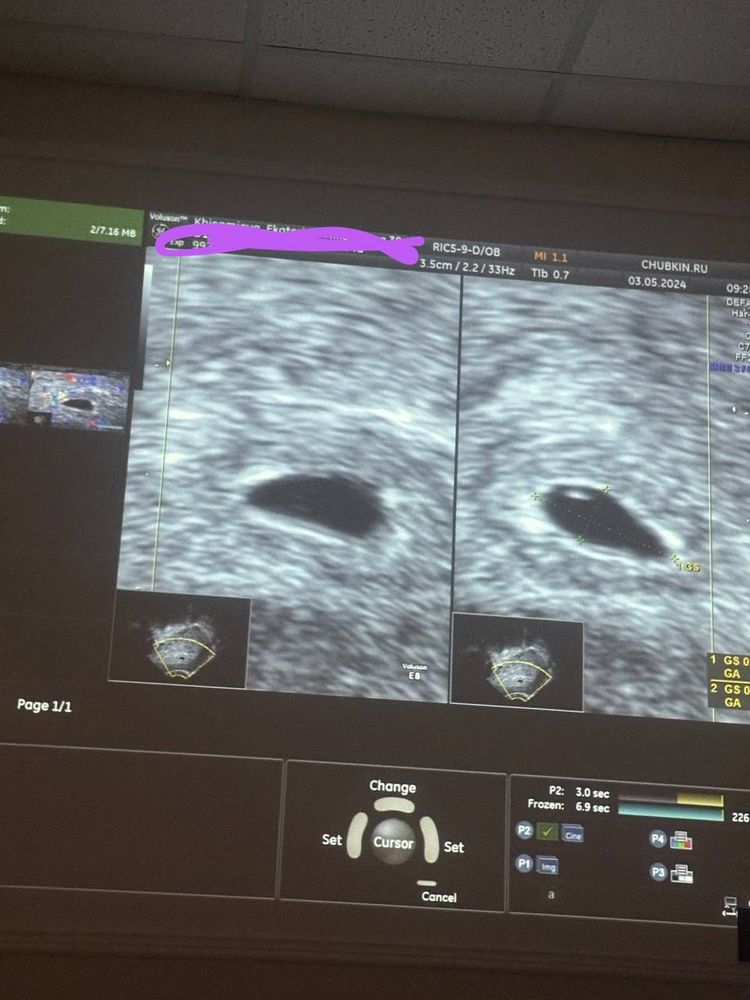

Сходили на первое узи ❤️👶, 14 дпп. ХГЧ на 13 дпп 1473

поздравляю с первыми фотками) теперь растите в срок, развивайтесь и получайте только самые лучшие эмоции от беременности